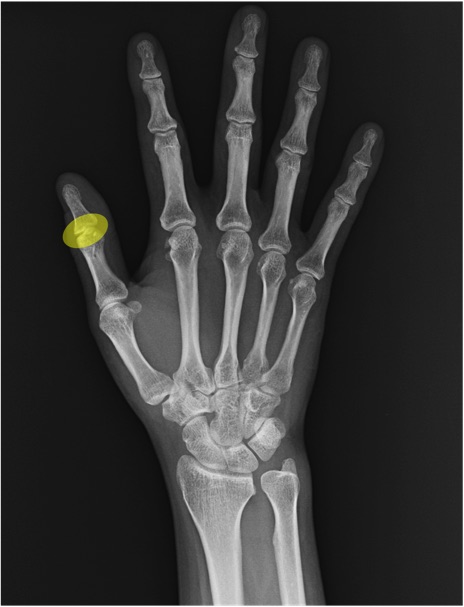

IP関節(interphalangeal joint)の手関節レントゲン画像における正常解剖

基節骨(proximal phalanx)

中節骨(middle phalanx)

末節骨(distal phalanx)

MP関節(metacarpophalangeal joint)

PIP関節(proximal interphalangeal joint)

DIP関節(distal interphalangeal joint)